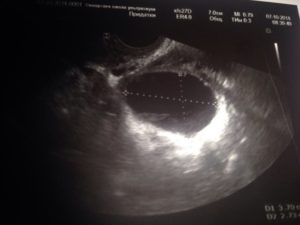

Размеры желтого тела сразу после овуляции составляют около 12 — 20 миллиметров. С каждым днем цикла ЖТ увеличивается в размерах, которые достигают своего пика к концу цикла, на 19-28 день. В это время нормальный размер ЖТ – 23-29 мм.

На УЗИ желтое тело определяется как округлое неоднородное образование.

Его видно и при методике исследования через брюшную стенку (трансабдоминальная методика УЗИ), но более достоверные результаты диагностики получают при трансвагинальном методе с использованием внутривагинального датчика.

По УЗИ диагностировать данную патологию можно при несоответствии размеров железы положенным (менее 10 миллиметров). Для уточнения диагноза пациентке проводят лабораторное исследование крови на концентрацию прогестерона.